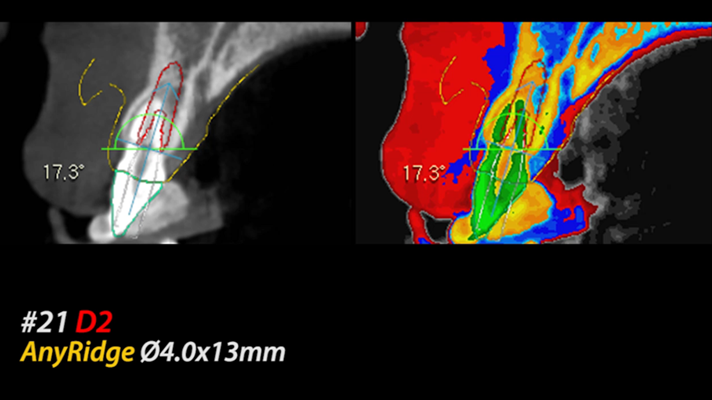

Clinical case: Extraction, immediate placement & loading using

R2GATE solution in aesthetic zone

- Courtesy of Dr. Jong-Cheol Kim, Korea-

Dr. Jong Cheol Kim, immediate loading, digital guided surgery, Digital ONE-DAY Implant, maxillary anterior, #21, guided surgery, immediate loading, AnyRidge, R2GATE, Mega ISQ, MEG Torq, R2GATE Full Surgical Kit

AnyRidge implant system, R2 Guide, R2GATE Full Surgical Kit, Mega ISQ